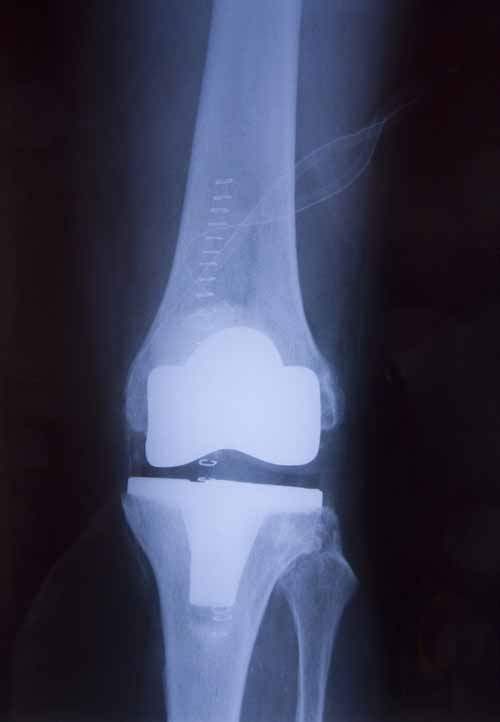

Protez cerrahisi; Omuz -kalça ve diz protezleri (eklemin yapay parçalarla değiştirilmesi) en ileri dünya standartlarına sahip "laminar air flow" lu ameliyathanelerinde, dünyanın en yüksek standartlarında en son geliştirilmiş protezler kullanılarak, uluslararası standartlarda eğitime sahip deneyimli ortopedistlerce yapılmaktadır.

Protez Cerrahisi: Yaşlıların kalça ve omuz kırık çeşitlerinden daha büyük kısmına uygulama şansı veren yeni protez dizaynları ile ameliyatın ertesi günü yürüme şansı veren uygulamalardır.